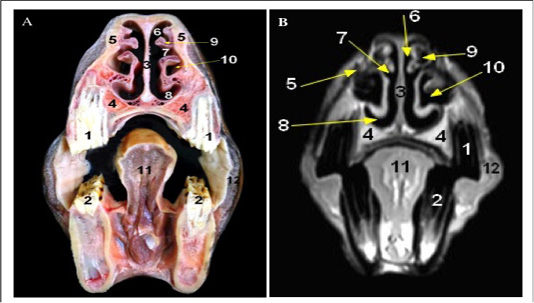

Cross sectional anatomy (Panel A) and MR image (Panel B) of horse head at the level of first and second premolar teeth. 1) Upper first and second premolar teeth; 2) Lower first and second premolar teeth; 3) Cartilaginous part of Nasal septum; 4) maxilla bone; 5) Nasal bone; 6) Dorsal nasal meatus; 7) Middle nasal meatus; 8) Ventral nasal meatus; 9) Dorsal nasal concha; 10) Ventral concha1 bulla; 11) Body of tongue; 12) Buccinators muscle.